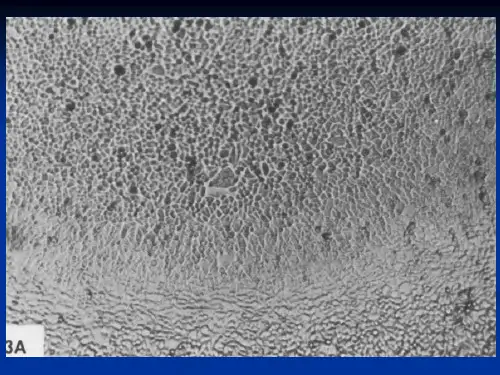

生物制品是以微生物、细胞、动 物或人源组织和体液等为原料, 应用传统技术或现代生物技术制 成,用于人类疾病的预防、治疗 和诊断的药品。

生物制品是应用普通的或以基因工程、 细胞工程、蛋白质工程、发酵工程等生 物技术获得的药品。 生物制品不同于一 般医用药品,它是通过刺激机体免疫系 统,产生免疫物质(如抗体)才发挥其功 效,在人体内出现体液免疫、细胞免疫或 细胞介导免疫。